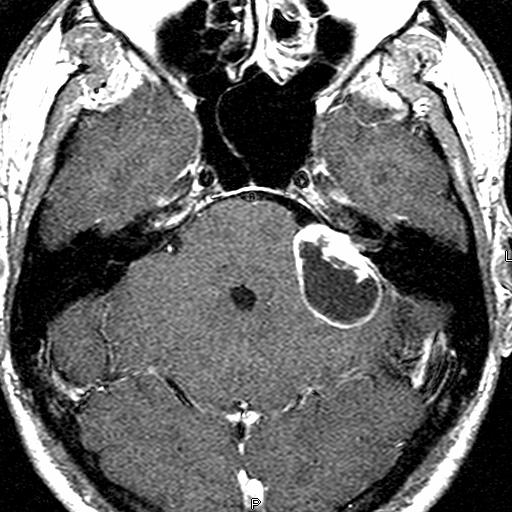

Acoustic NeuromaDefinition: An acoustic neuroma is a benign tumor that grows from the lining of one of the vestibulocochlear nerves, the nerves responsible for hearing and balance.

Evaluation: The best way to assess an acoustic neuroma is with an MRI of the brain.  A CT scan may be recommended to evaluate the skull around the tumor.  Audiometry, a test of hearing, may be ordered to assess the extent and progression of a person’s hearing loss.